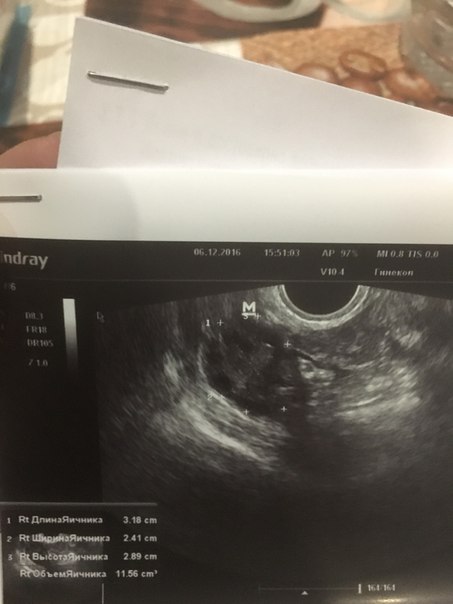

Помогите кто нибудь.Нет деток и никакого аборта ни викидыша ничего 5 лет.живу с мужем.мне 22.все эти 5 лет по врачам по больницам.в сентябре была чистка.на днях на УЗИ .сказали все плохо срочно что то делать иначе климакс в 23 года.что делать неужели это конец приложу результаты УЗИ и гормонов.может кто сталкивался.поделитесь

Я 6 шт фолликов насчитала в яичнике, очень хороший эндометрий,при чем тут климакс ( странный доктор)??? Проблема в гормонах, снижайте пролактин и рожайте на здоровье)))

Они не лопаются и не созревают.доктор говорит что яичники спят и не работают.кровотечение по месяцу идет из за поликистоза.жду анализа на оставшийся резерв фолликулов.так как она говорит что яичники пусты лишь железистая ткань

Так мне и сказали что яичники пустые не работают.Овуляция не происходит.

Овуляция не происходит это еще не климакс. Это на СПКЯ похоже больше.

Очень похоже на спкя, не ставили вам такой диагноз?

Да поставила поликистоз